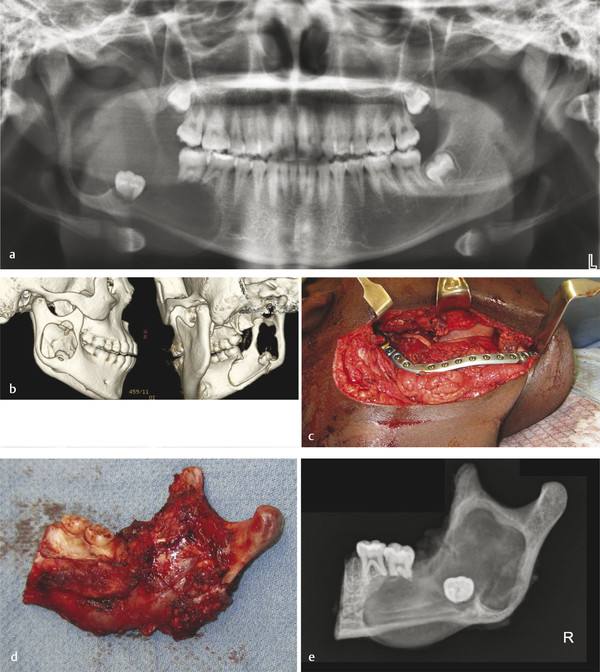

Ameloblastoma is the most common odontogenic tumor, with about 50% of them occurring between 20 and 40 years of age. In the pediatric population, ameloblastoma must be considered in the differential diagnosis of any unilocular or multilocular radiolucency. Unicystic ameloblastoma represents about 5% of all ameloblastomas and tends to occur in younger age range (10–24 years) (Fig. 9‑11a, b). For all ameloblastomas, 80% occur in the mandible and 75% in molar–ramus region. They are benign, locally aggressive, expansile neoplasms that commonly cause dental changes such as mobility, tooth displacement, and root resorption. Untreated tumors can progress to a tremendous size. Treatment involves resection with 1.0 to 1.5 cm bony margins and one uninvolved anatomical barrier (Fig. 9‑11c, d). Consider frozen sections of soft tissue margins as well as taking a radiograph of the specimen to ensure that you have 1-cm margins past radiographic margins (Fig. 9‑11e). Cure rate with resection is about 98%. Controversy exists around immediate reconstruction at the time of resection versus a staged approach. If enucleation and curettage are performed, there is a recurrence rate of more than 80% (Fig. 9‑12).